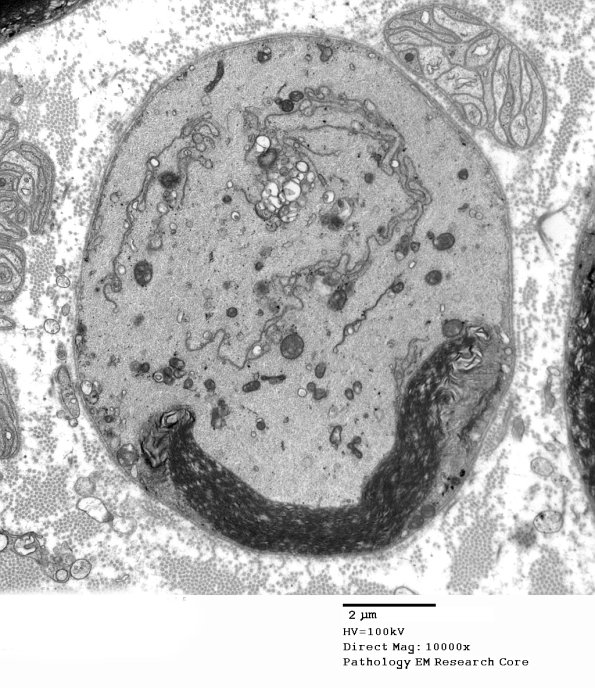

16B1-5 The “half myelin” artifact is associated with protruding invagination of thin processes from the axolemma. We wondered if this was the same process as the Schwannian honeycombs of Asbury and Johnson in which abnormal axonal organelles are sequestered/phagocytosed from the axoplasm by Schwann cell processes. The axoplasm appears to contain filamentous organelles. (electron micrographs)